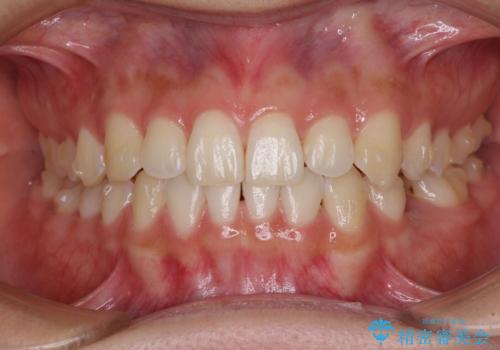

- 前歯の叢生と、奥歯の咬み合わせの悪さを気にして来院された患者様です。

左下には後続永久歯の欠損した乳歯が残存しており、叢生を相まって咬合関係が乱れていました。

乳歯は抜歯し、インビザラインにて矯正治療を行いながら、並行してインプラントによる補綴治療を行うこととしました。

矯正治療が終わるタイミングに合わせてインプラントの埋入を行っていたので、矯正治療を終了すると同時にセラミック補綴治療を行えました。

短期間でしっかりと治療を終えることができました。